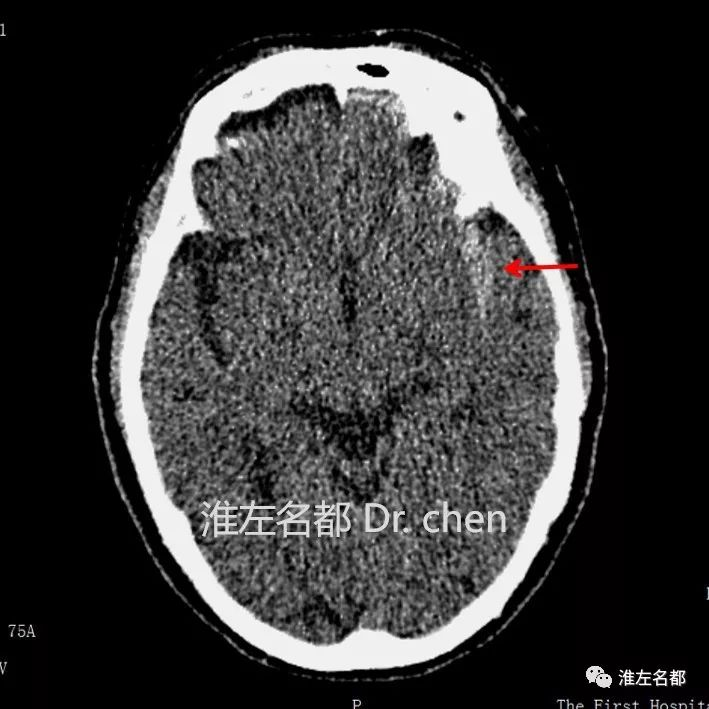

△CT平扫:左侧侧裂池高密度影(红箭),提示蛛网膜下腔出血。